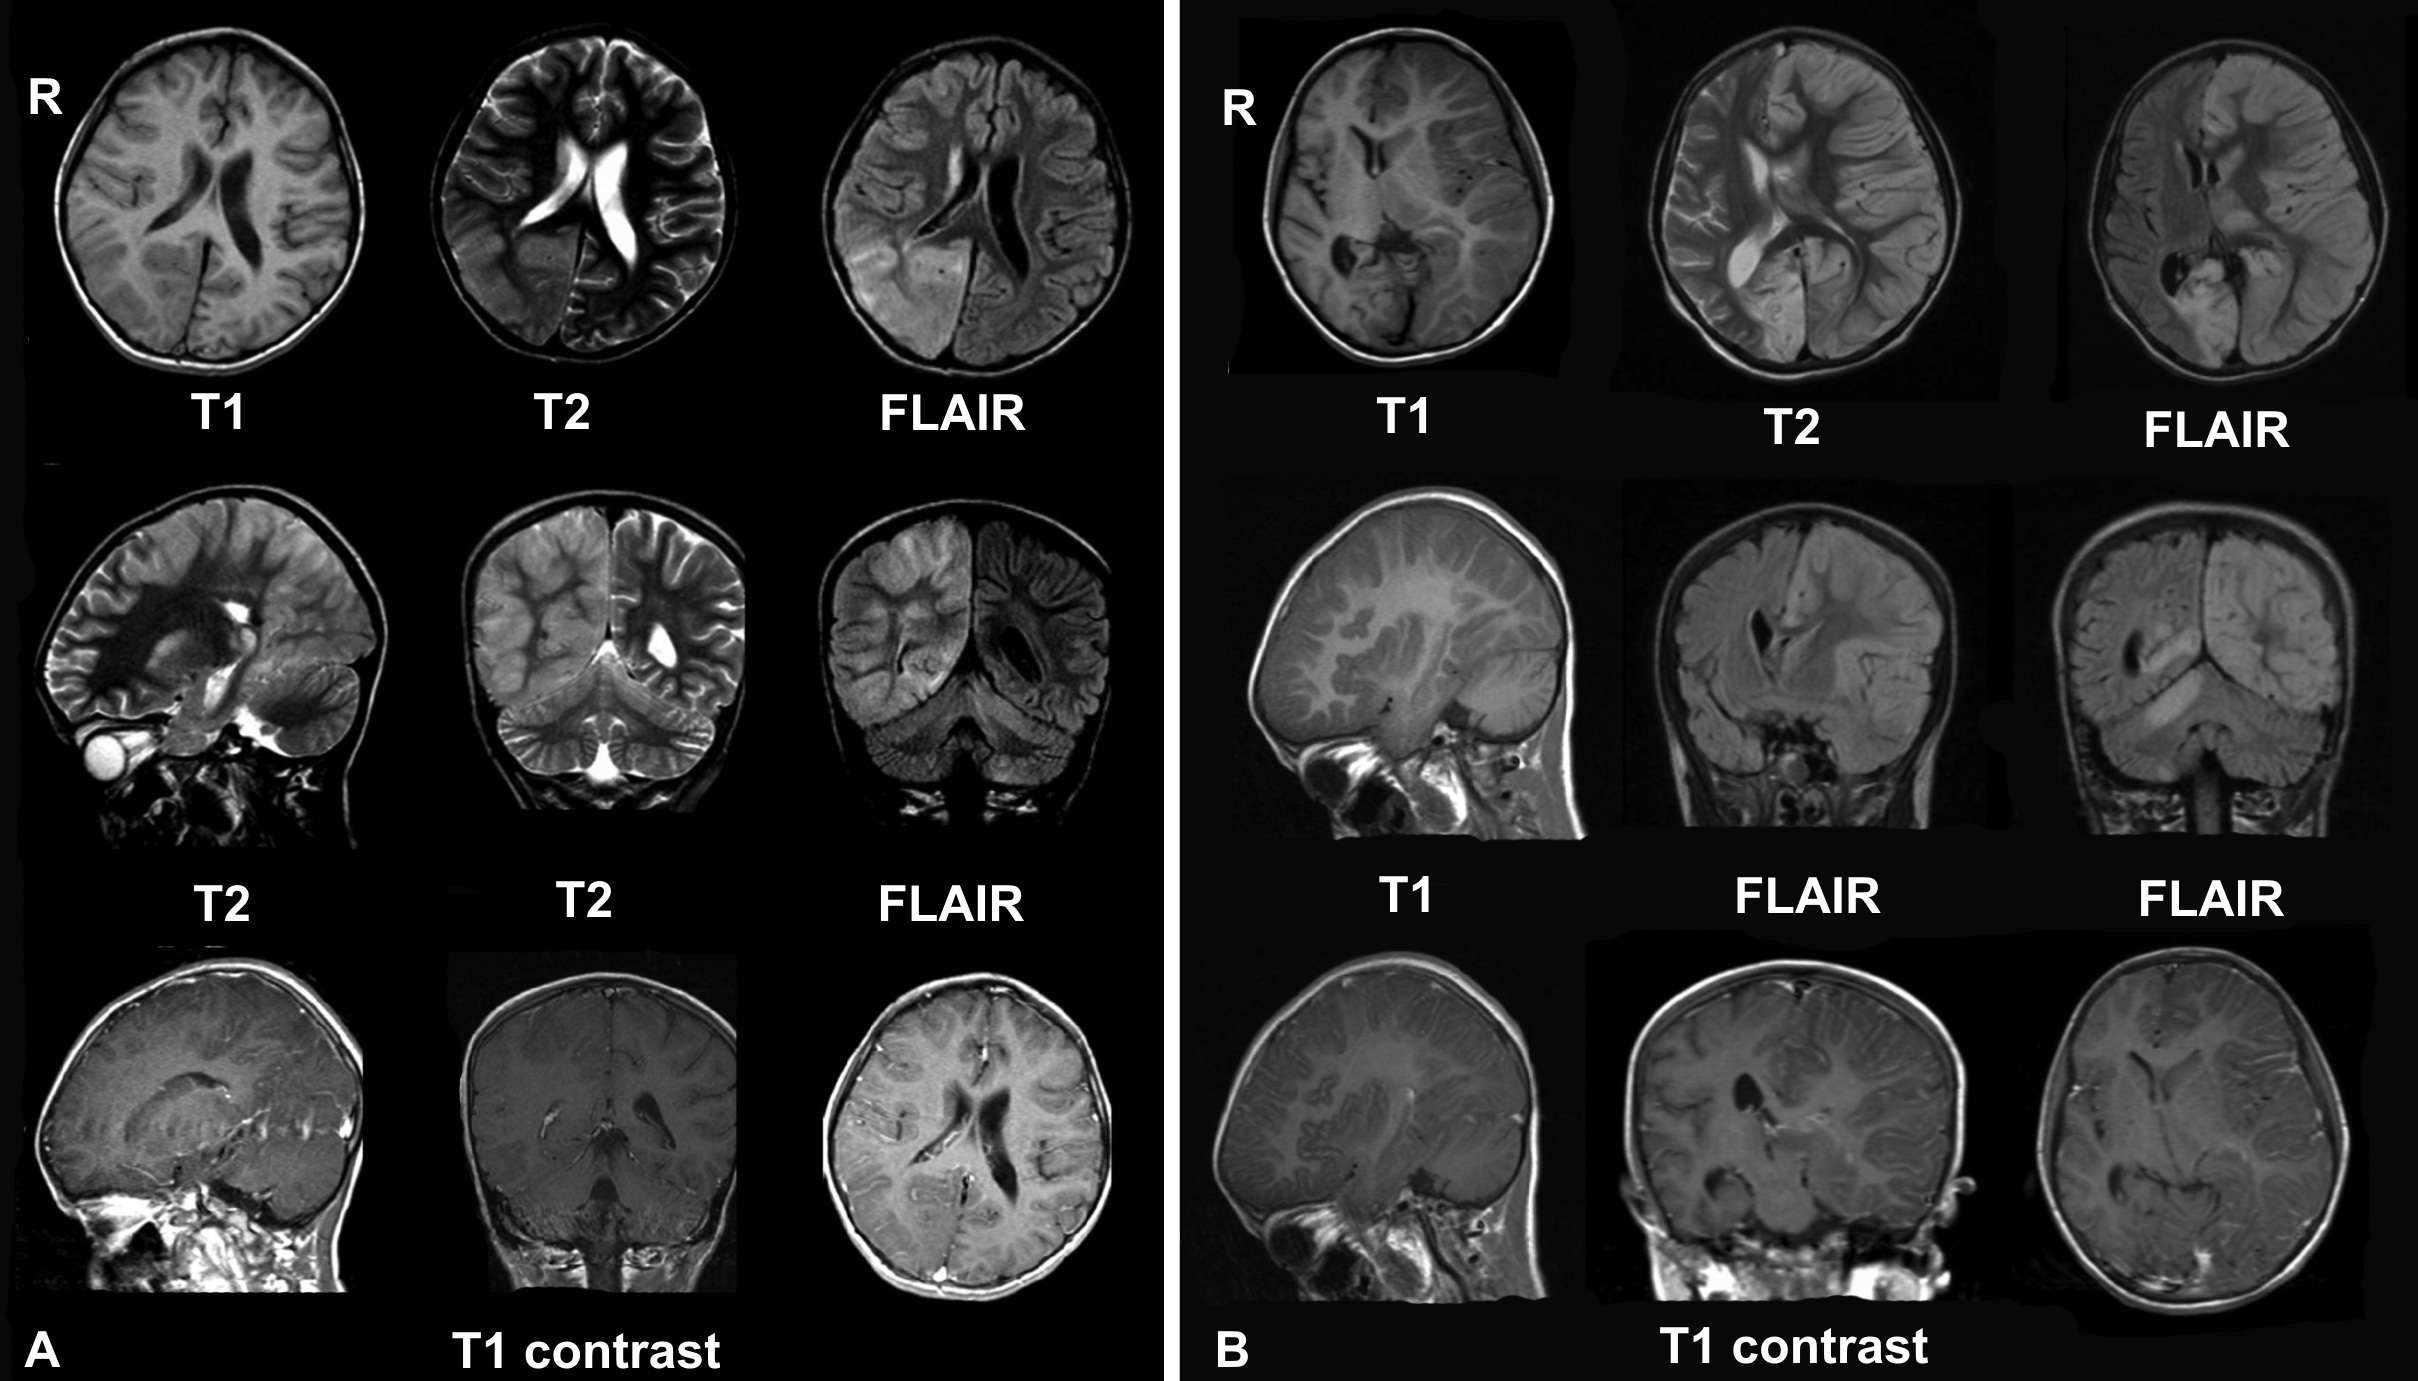

Difference Between Meningitis and Encephalitis